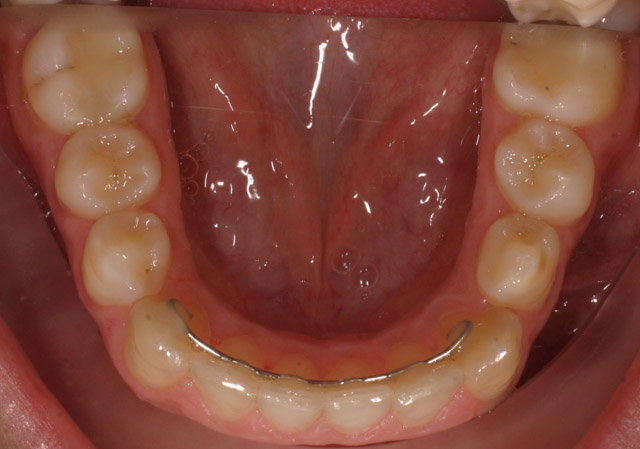

4035 visualizzazioni Trattamento eseguito con tecnica linguale 2D della RMO in un lasso di tempo molto breve, in paziente adulta con grandi esigenze estetiche.

Al fine di allineare gli elementi dentari si è ricorso allo stripping selettivo nel settore incisivo con una contenzione funale con retainer fisso; durata del trattamento da febbraio 2009 con debonding a ottobre 2009 ( 8 mesi ).